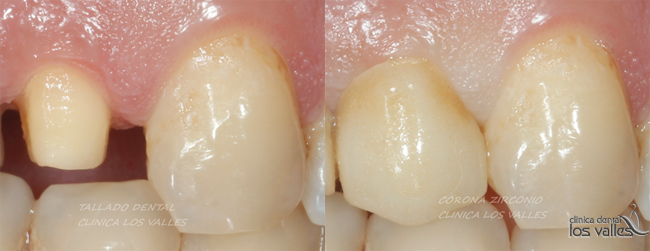

Esta rehabilitación consistiría en la reconstrucción en composite de alta estética, realizando protección cuspídea con o sin poste de fibra de vidrio, para evitar la posible fractura o, en casos de piezas muy dañadas y molares donde se ejerce mucha fuerza masticatoria, la colocación de fundas o coronas de circonio para asegurar la longevidad de las muelas endodonciadas.